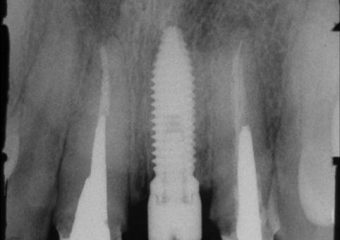

Rx com o implante já instalado